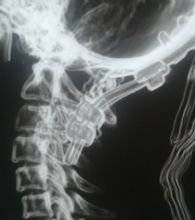

9月2日,我院神经外科在解放军昆明总医院封亚平教授的指导下,成功实施县内首台上颈椎、颅颈交接区手术,这标志着我院神经外科诊疗技术又迈上了一个新台阶。 40岁女性患者,因“头疼头晕伴左侧肢体麻木3年余,加重1月”入院,诊断为环枕畸形合并小脑扁桃体下疝。MRI及CT显示:枕颈融合,寰枢关节脱位,颅底陷入,颅颈角明显变小,小脑扁桃体下疝、延颈交界脊髓明显受压(如图下图所示),此病的症结是那块骨头(红色箭头处)压迫了神经! 想要解决问题,自然就得把那块骨头“掰”下来。骨头虽小,真要把它“掰”下来却绝非易事,需要把颈1-2的小关节撑开,但是,患者的小关节后面还有很粗大的动脉血管(蓝色箭头)挡着,手术难度相当大! 经解放军昆明总医院封亚平教授会诊,我院神经外科为该患者实施了后入路枕骨大孔区减压、寰枢椎脱位复位、枕颈固定、植骨融合术,手术用时短短1.5小时,出血量仅50ml。病人术后神经压迫症状明显改善,第一天开始进食,第二天即可下床活动。 (斜坡颈椎角增大到正常) (术后复查CT及MRI显示寰枢关节脱位复位理想,颅颈角增大基本正常,脊髓受压解除。) (术中无血管、神经损伤) 寰枕畸形是枕骨大孔区、寰枢椎骨质发育异常伴神经系统、椎动脉及附近软组织发育异常的一种先天性畸形疾病。寰枕畸形主要包:扁平颅底、颅底凹陷、寰枕融合、颈椎分节不全、寰枢椎脱位、小脑扁桃体下疝畸形。寰枕畸形可继发于畸形性骨炎、软骨病、佝偻病等。寰枕畸形患者早期临床表现为颈短、头颈痛、活动受限等。对于颈部粗而短的人群而言,寰枕畸形的发病可能相较一般人更高。原因在于,颈部粗短的人在转头活动的过程中,关节的活动度比较大,磨损的程度也更高,因而更容易发病。寰枕畸形合并小脑扁桃体下疝及脊髓空洞症为先天性发育不良所致,成年起病,无任何药物可治疗,手术是唯一有效的治疗办法。起初,患者会逐渐出现颈肩部疼痛,手臂麻木、无力,行走不稳等症。若不及时治疗,晚期预后会很差。(图为 邓泽亮 编辑 雅玲) 神经外科电话0739-2570859 科主任邓泽亮13975968148 副主任黄敏15211991811 |